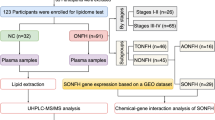

Metabolomic approaches were employed in this study to detect biomarkers of early-stage NTONFH (22 patients, 23 controls), based on the platform of ultra-performance liquid chromatography tandem quadrupole time-of-flight mass spectrometry (UPLC-QTOF-MS) and the uses of multivariate statistic analysis, putative metabolite identification, metabolic pathway analysis and biomarker analysis.

The study subjects consisted of 50 outpatients and 25 volunteers. Patients diagnosed with NTONFH and healthy controls were respectively recruited from Orthopaedic Outpatient Department and Health Examination Center, the First Affiliated Hospital of Chongqing Medical University between December 23rd, 2015 and April 22nd, 2016. Diagnostic criteria for NTONFH were according to the recommended standards for Japanese population (Sugano et al. 1999), and the stage of the disease was based on the modified Ficat-Arlet classification of osteonecrosis of the femoral head (Banaszkiewicz 1985). Erythrocyte sedimentation rate (ESR), C-reactive protein (CRP), X-ray of pelvis, and MRI of both hip joints were performed in all of the participants. Inclusive criteria for NTONFH group were as followed: (1) diagnosed with osteonecrosis of the femoral head; (2) no history of hip trauma; (3) staged between 0 and II using Ficat-Arlet classification; (4) not any inflammatory arthritis complicated (e.g., rheumatic arthritis); (5) not any metabolic disease complicated (e.g., rickets); (6) no drug taken in last 4 weeks. Inclusive criteria for control group were as followed: (1) never suffered from hip pain or dysfunction; (2) no osteonecrosis or any other joint diseases observed on radiographs or MRI scans; (3) with normal values of ESR and CRP; (4) not any inflammatory or metabolic disease complicated. Finally, there were 22 NTONFH patients and 23 healthy controls eligible to be included under above criteria.

There were 23 NTONFH patients and 22 healthy controls included eventually with 27 patients (21 classfied Ficat III or IV, four influenced by recent NSAIDs intake, one accompanied with rheumatoid arthritis, and one with uncertain history of trauma) and three controls (with abnormal levels of both ESR and CRP) excluded. No statistical significance was detected in terms of age (NTONFH 51.86 ± 12.2, control 53.43 ± 16.78, p = 0.72), sex (NTONFH 16M + 6F, control 15M + 8F, p = 0.75), or BMI (NTONFH 23.23 ± 3.27, control 24.53 ± 3.64, p = 0.22) between the two groups. Image manifestations of the two groups were displayed in Fig. 1.